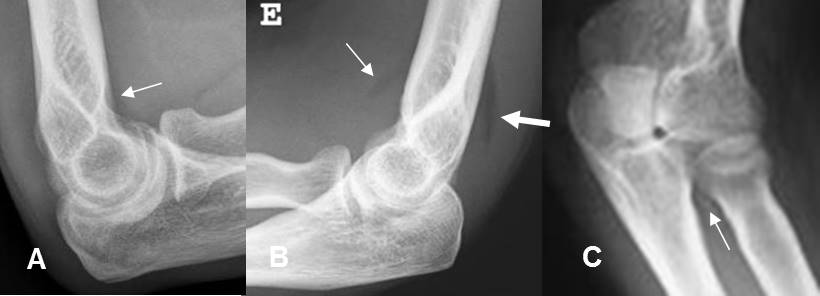

La radiografía (Rx) simple es la modalidad de elección inicial, para la valoración del trauma. (1). Las lesiones articulares son difíciles de diagnosticar con Rx simple, si solo hay lesión ligamentaria. Se deben sospechar por la presencia de derrame articular, que produce desplazamiento o pérdida de los planos grasos. (1). (Fig 2).

Fig 2. Derrame articular.

A: Rx lateral. Cojinete anterior, en un paciente normal.

B: Rx lateral. Visualización del cojinete graso anterior (Flecha delgada) y el posterior, siempre patológico y que indica derrame articular. (Flecha gruesa). No se aprecian fracturas.

C: Rx oblicua. Fractura desplazada de la cabeza del radio.